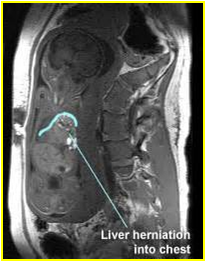

【产前诊断(Prenatal diagnosis)】

胎儿超声与MRI:可见胎儿胸腔内有腹部脏器